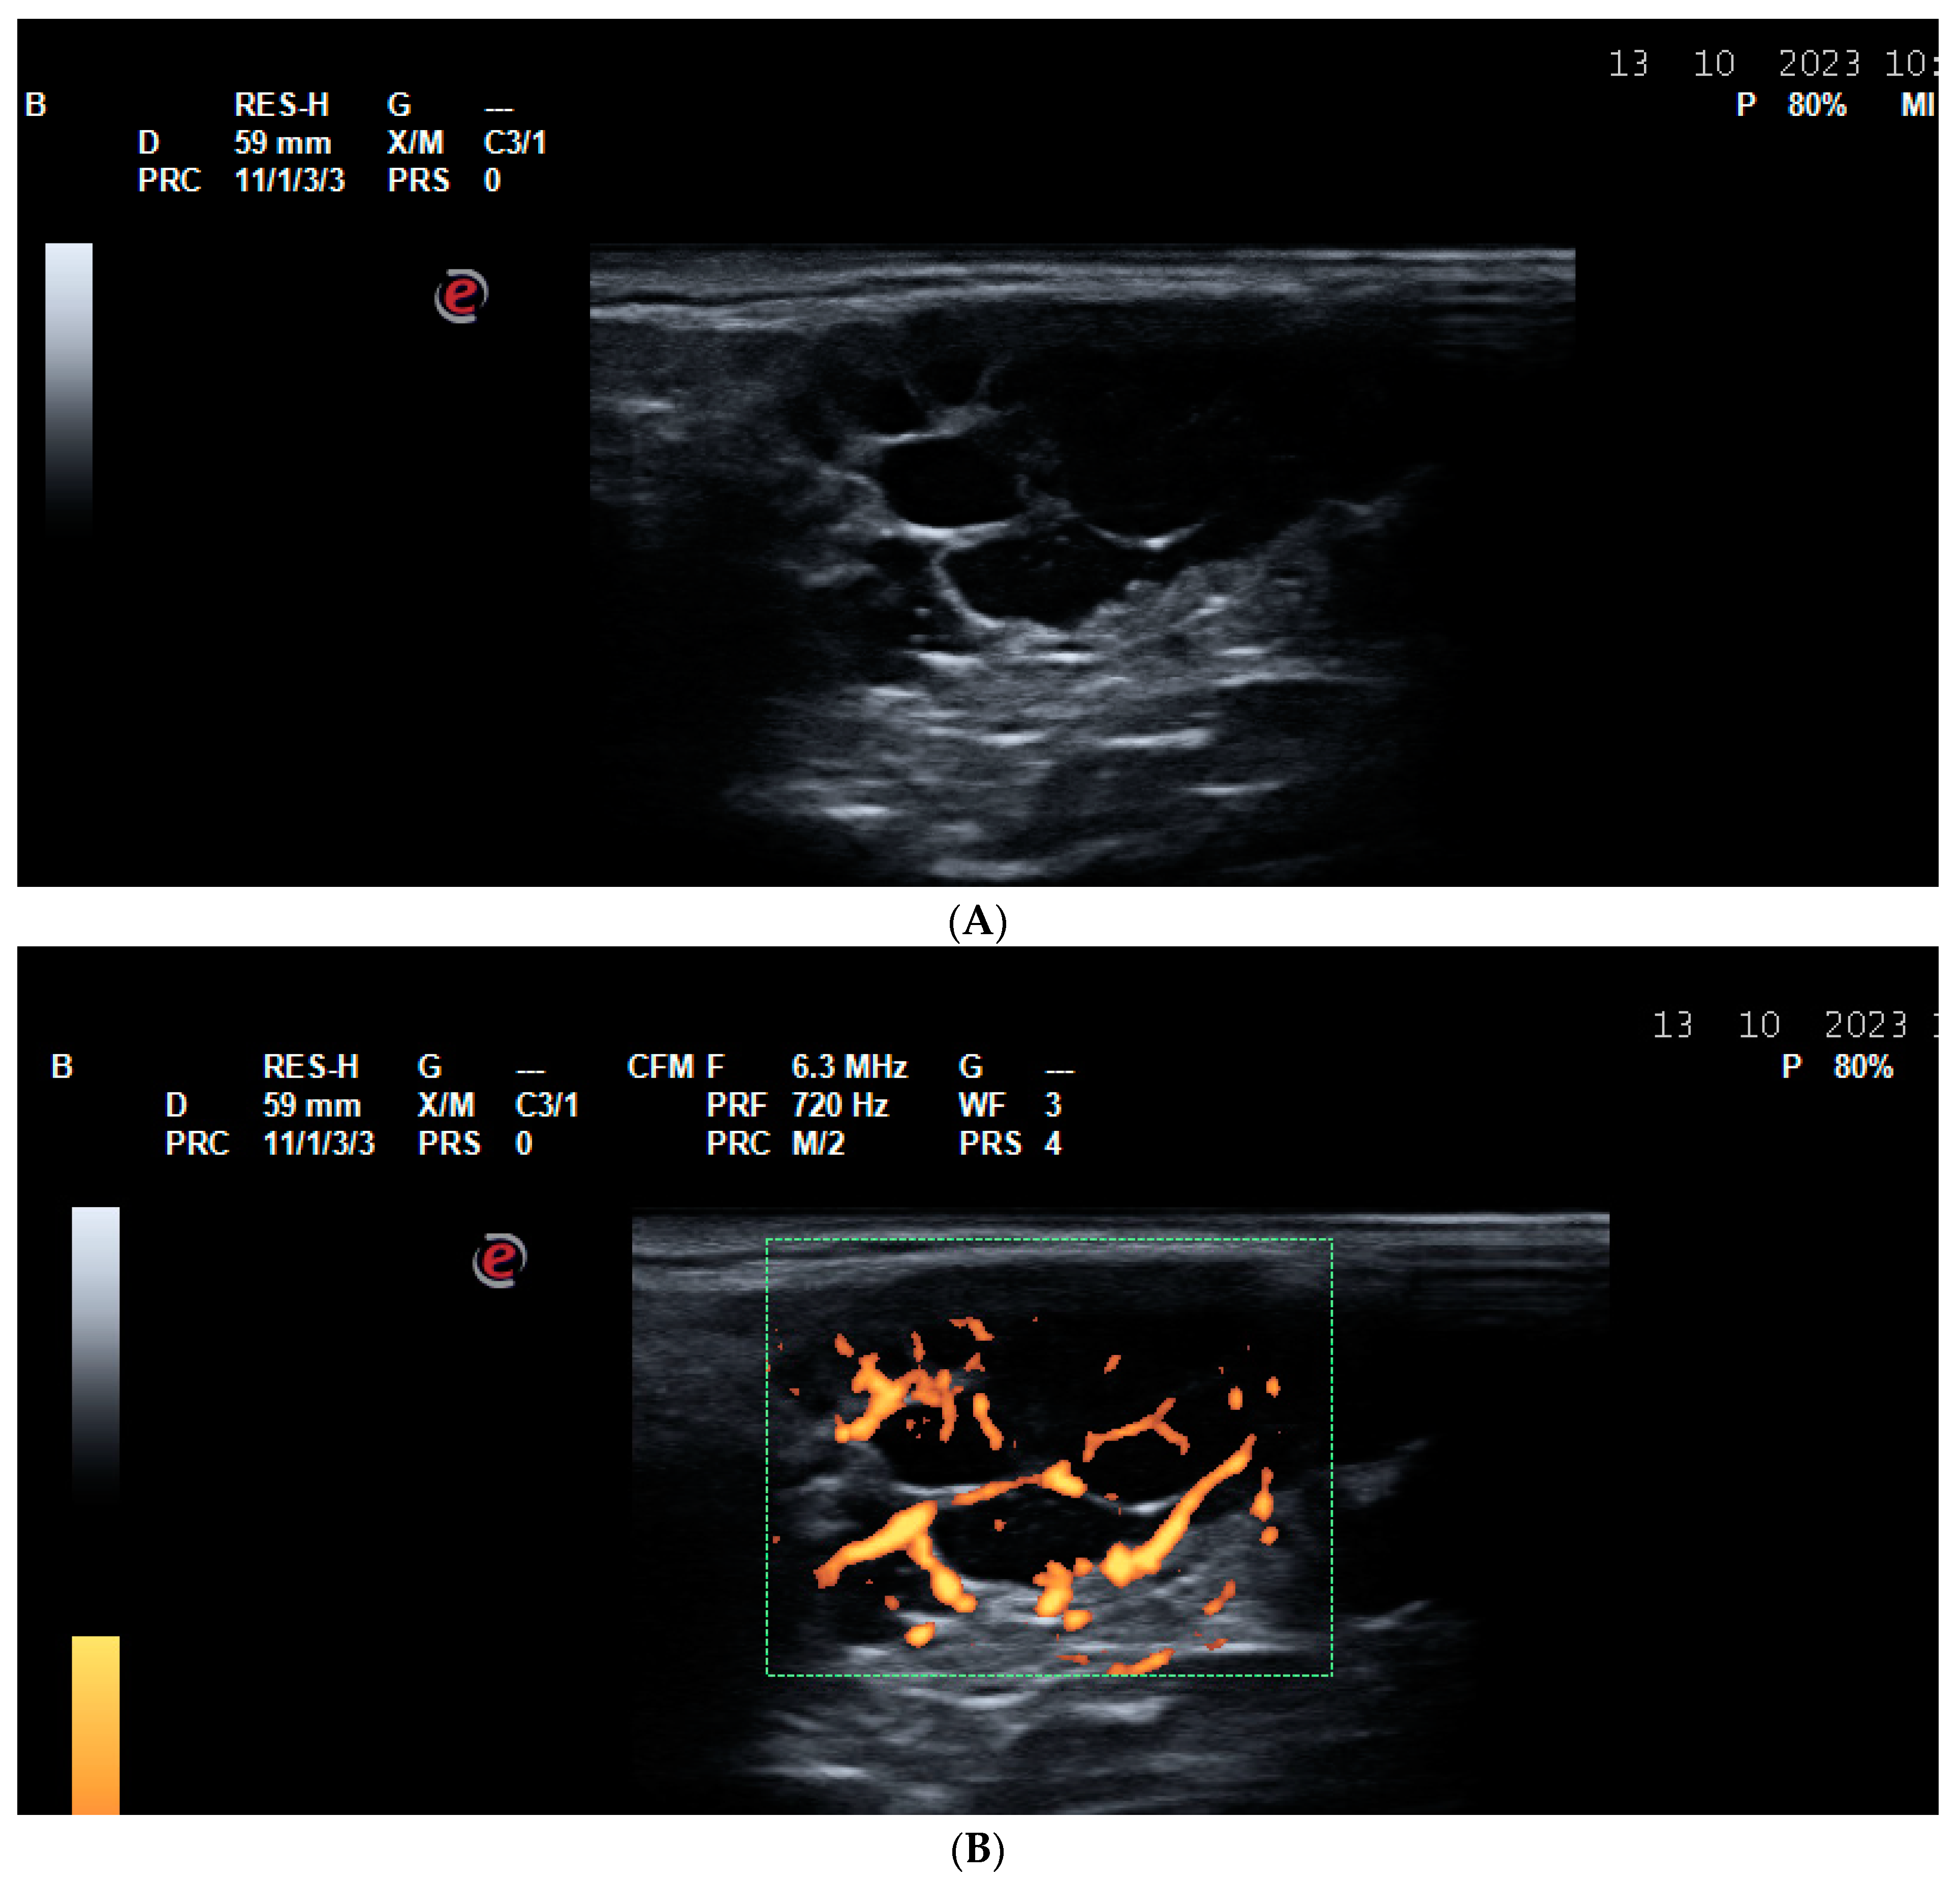

6. US for Assessment of Peripheral Nerves

- Lawande, A.D.; Warrier, S.S.; Joshi, M.S. Role of ultrasound in evaluation of peripheral nerves. Indian J. Radiol. Imaging 2014, 24, 254–258. [Google Scholar] [CrossRef] [PubMed] [PubMed Central]

- Schwabl, C.; Schmidle, G.; Kaiser, P.; Drakonaki, E.; Taljanovic, M.S.; Klauser, A.S. Nerve entrapment syndromes: Detection by ultrasound. Ultrasonography 2023, 42, 376–387. [Google Scholar] [CrossRef] [PubMed] [PubMed Central]

- Shaukat, A.; Aamir, H.; Ahmad, Z.; Ahmad, U. Diagnostic accuracy of ultrasonography in diagnosis of Carpal Tunnel Syndrome. Pak. J. Med. Sci. 2024, 40, 753–756. [Google Scholar] [CrossRef] [PubMed] [PubMed Central]

- Ratasvuori, M.; Sormaala, M.; Kinnunen, A.; Lindfors, N. Ultrasonography for the diagnosis of carpal tunnel syndrome: Correlation of clinical symptoms, cross-sectional areas and electroneuromyography. J. Hand Surg. Eur. Vol. 2022, 47, 369–374. [Google Scholar] [CrossRef] [PubMed]